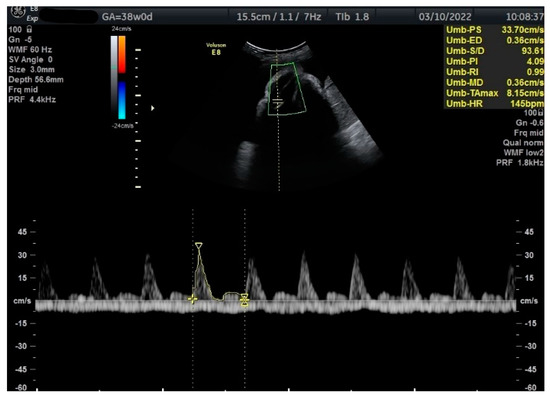

Figure 2.

Doppler measurement at 38 + 0 weeks of normal TA-PI (measured manually).

Measurements of the TA-PI were taken using Doppler on the lower extremity where the tibial and fibular bones were clearly visible. The angle between the transducer and the bones was adjusted to 45° or less. The color Doppler gate was placed over the vessel in the leg between the two bones to locate the anterior TA (Figure 1). We were able to measure the velocity of the TA in all fetuses, signals were recorded over at least 5–6 cycles with an equal shape and amplitude of the blood flow waveforms (Figure 2 and Figure 3).